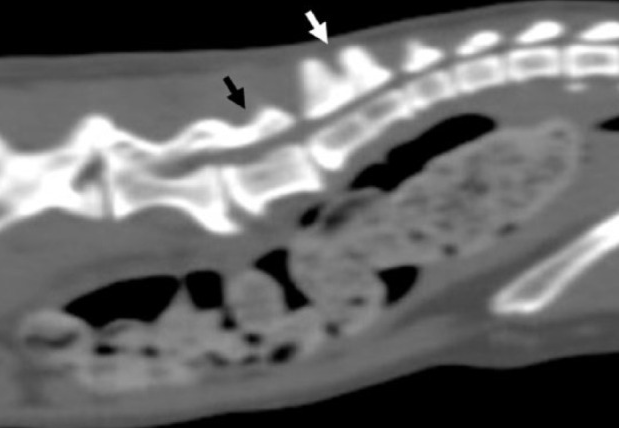

고양이 요천추간 이상 병변은 흔하게 관찰되는 병변이다.

즉, 요천추의 이상이 선천적이든 후천적이든, canal stenosis와 변비 발생 가능성을 높인다는 것. 무시할 수 없는 영역의 문제로 방사선 검사에서 관찰된다면 해당 고양이는 반복적으로 이상 여부를 평가하기 위한 건강검진을 정기적으로 받아 야한다는 말이다.